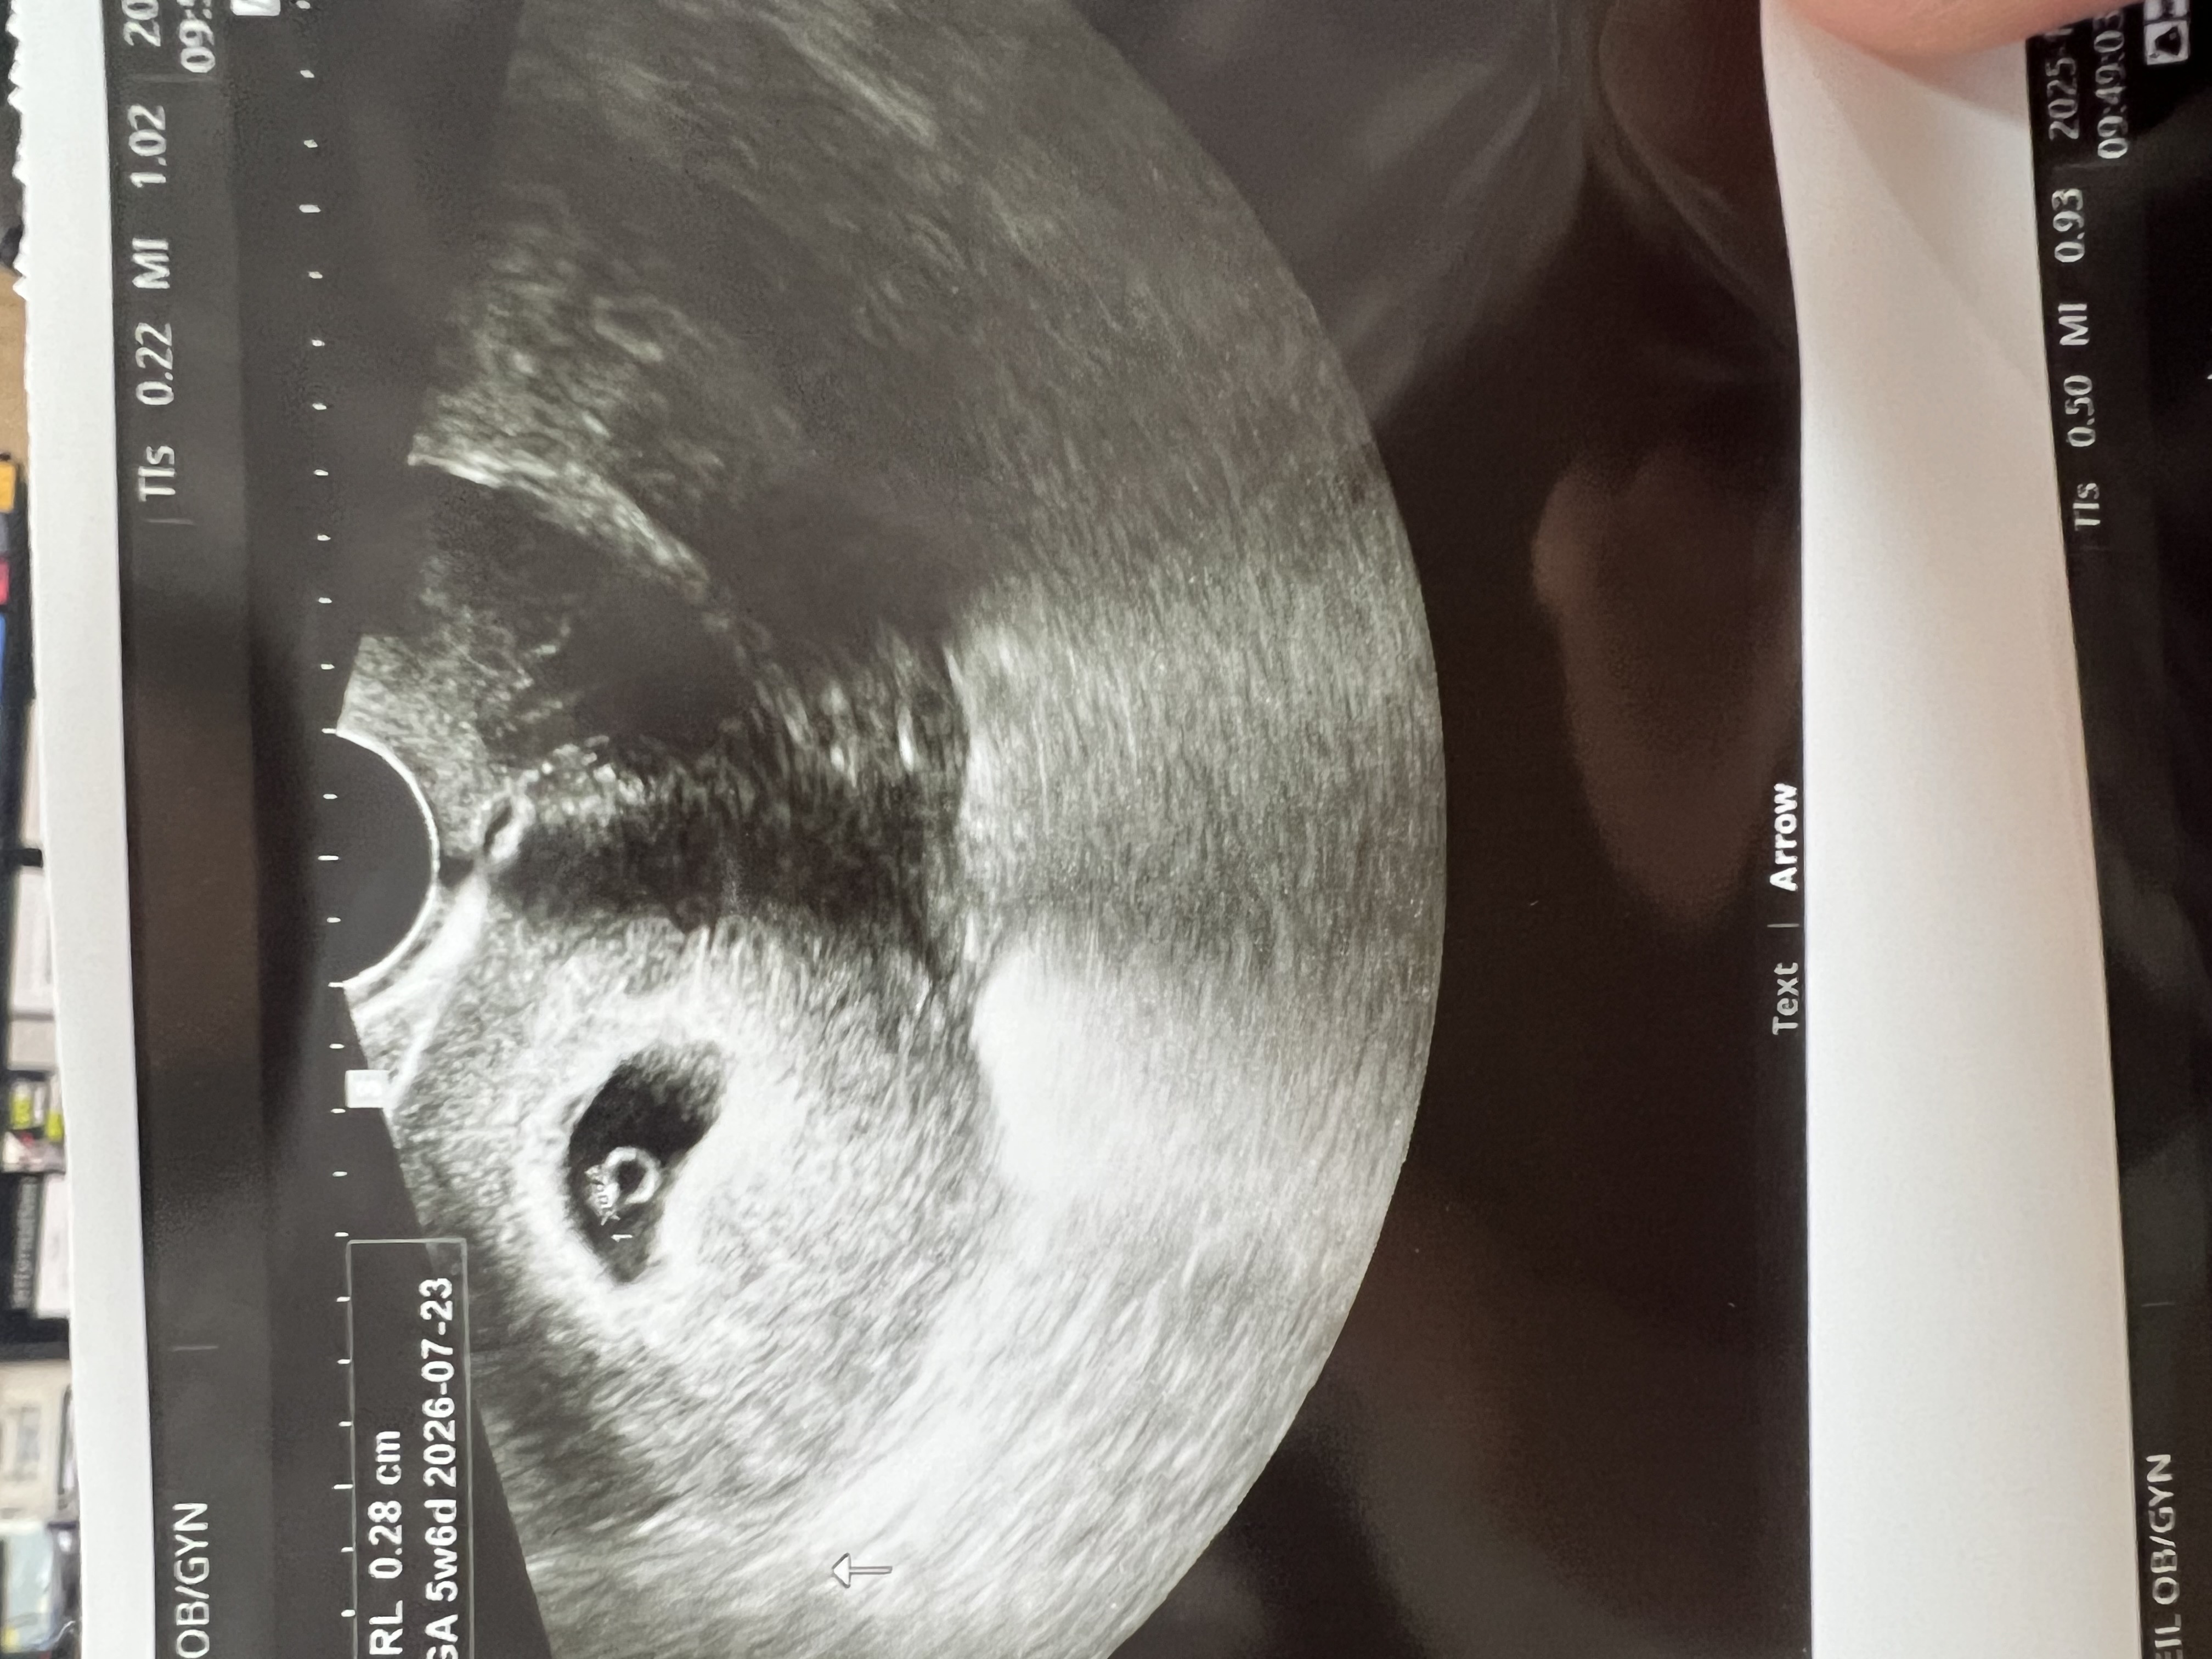

난황의 위치에 따라

벌써부터 성별이 궁금한 예비맘입니다. 난황의 위치를 보면 성별을 예측할 수 있다고들 하는데 제 난황 한 번 봐주세요.ㅠ